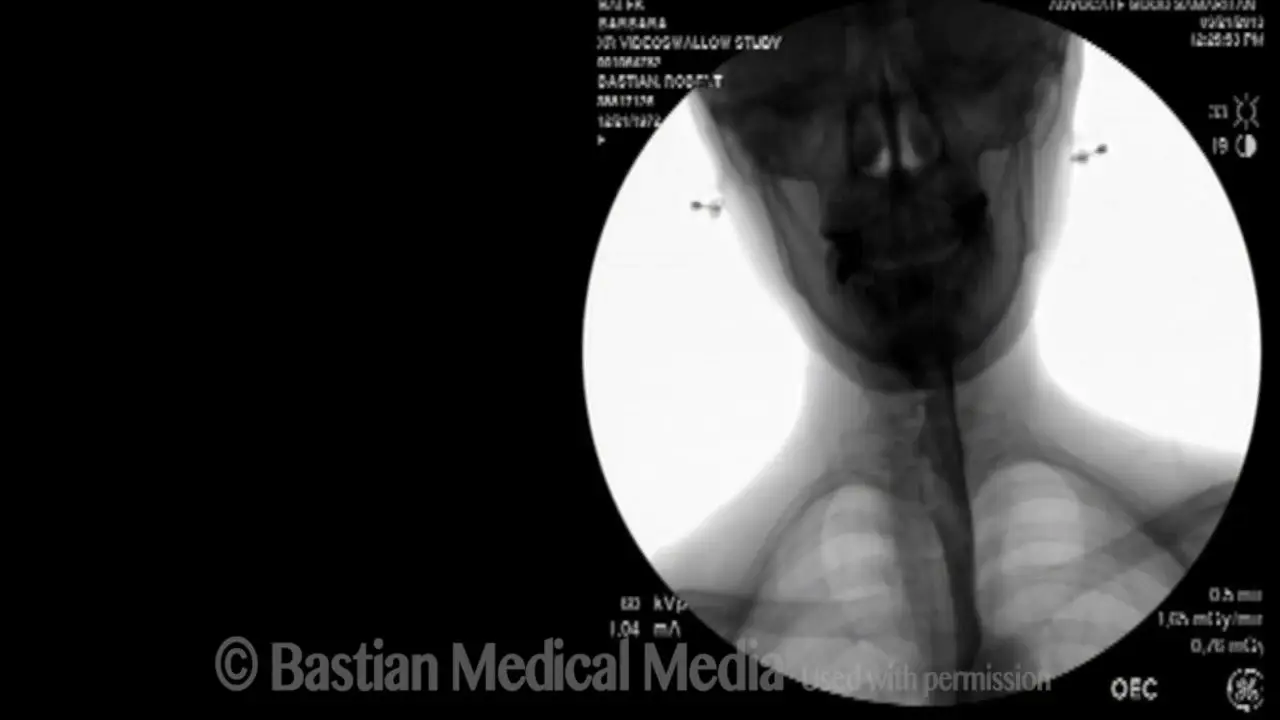

Аспирационная пневмония у новорожденных является серьезным состоянием, которое может иметь различные последствия для здоровья ребенка. Врачи отмечают, что данное заболевание возникает, когда инородные вещества, такие как амниотическая жидкость или пища, попадают в дыхательные пути. Это может привести к воспалению легких и нарушению газообмена.

Возникает аспирационная пневмония у маленьких деток вследствие вдыхания ребенком инородного вещества (например, это может быть еда, материнское молоко, частички рвоты и т.д.). Если родители вовремя не среагируют, патология может привести к абсцессу легкого, или, что еще страшней, к гибели малыша (особенно актуально для деток в первые месяцы жизни).

У новорожденного ребенка аспирационная форма пневмонии может развиваться в случае, если ребенок заглотнул околоплодные воды.

Как уже говорилось выше, причиной аспирационной пневмонии становится аспирация жидкости в бронхи или инородных тел. Выделяют следующие причины, вызывающие воспалительный процесс: